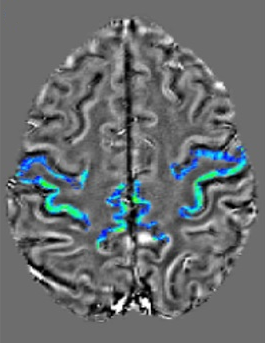

47 ALS patients, 23 healthy controls (HC), and 15 ALS Mimics (ALS-Mim) were retrospectively recruited. Among the ALS patiens, 12 with predominant UMN impairment (UMN-ALS), 16 with predominant LMN imparment (LMN-ALS), and 19 with no clinically-defined predominance (c-ALS). MRI scans were performed in a 3T SIGNA General Electric unit and included: 3D sag FSPGR BRAVO T1-weighted images (TR=8.7 ms, TE=3.2 ms; TI=450 ms; voxel size=1x1x1 mm, flip angle=12°; matrix 256x256); 3D spoiled gradient-echo multi-echo pulse sequence (TR=39 ms; 7 echoes with TE1=24 ms and ΔTE=3.3 ms; voxel size=0.468x0.468x1.4 mm; flip angle=20°; matrix 416x320). The visual assessment was performed by the Motor Cortex Susceptibility (MCS) score based on the visual inspection of the SWI hypointensity in the precentral cortex [6] shown in Fig. 1, a-b. The automatic assessment was performed by Freesurfer segmentation, quantitative susceptibility mapping (QSM) using STI Suite (Fig. 2) and computation of the skewness of the susceptibility values in the precentral cortex (SuscSkew) [4].

Quantitative Susceptibility Mapping (QSM) of the precentral gyrus automatically segmented